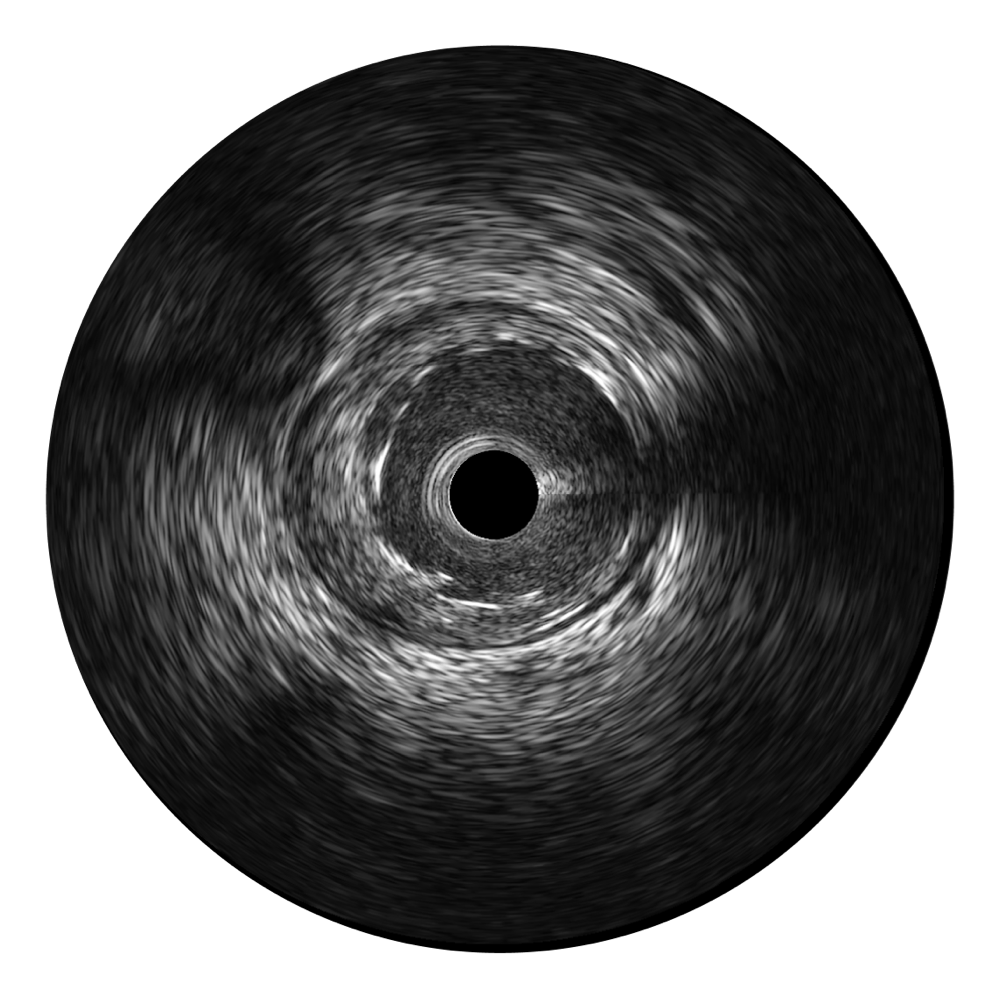

传统IVUS图像

对比传统IVUS导管成像,银河优越会宽频IVUS图像的近场支架梁显影更细腻,远场中膜外血管仍清晰可辨,兼顾远中近,兼顾分辨力与穿透深度